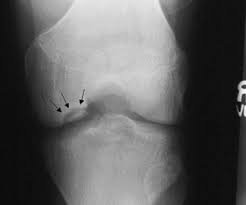

Рентгенологічні методи — як рентген, так і КТ-сканування — вже давно служать важливими інструментами у виявленні хвороби Крона. Це наче хірургічний ніж, але без розрізу. Надають змогу побачити, що відбувається всередині організму, без зайвих ризиків та болю.

- Рентген живота — дозволяє виявити неспецифічні зміни, часто використовується як початковий етап обстеження.

- КТ-сканування — дає глибше розуміння стану тканин, дозволяє зробити детальні знімки у поперечних зрізах.

- Іригоскопія — рентгеноскопічне дослідження, при якому оцінюється стан товстої кишки після введення контрасту.

Такий метод, як рентген, має свої плюси: швидкість, доступність, точність у виявленні структурних змін. Але є і мінуси — не показує функціональних порушень, наприклад.